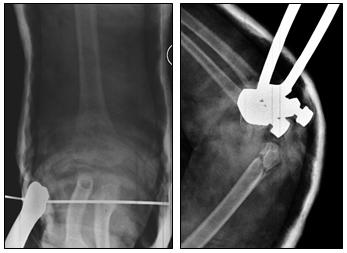

Anche nel trattamento dei distacchi epifisari tibiali distali il trattamento elettivo è conservativo. E’ necessaria tuttavia un riduzione anatomica in modo da ripristinare la continuità della placca cartilaginea ed evitare la formazione di ponti ossei di epifisiodesi che comporterebbero successiva dismetria o deformità.

In caso di riduzione imperfetta o perdita di riduzione in gesso si ricorre al trattamento chirurgico.

In tutti i casi (sia nel trattamento conservativo che chirurgico) è necessaria la contenzione in apparecchio gessato per 30 giorni. Successivamente in base alla evoluzione dei processi riparativi può essere avviata la mobilizzazione articolare evitando il carico per almeno 3 mesi. Torna su